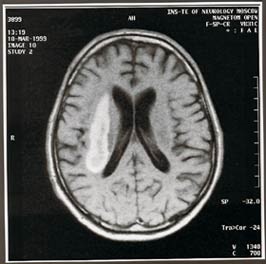

Primul este o hemoragie cerebrală din cauza ruperii navei sau, dimpotrivă, blocarea unui vas care furnizează creierului din cauza unui cheag de sânge sau o lacrimă-off „overgrowth“ a lumenului unei placi aterosclerotice.

80% din toate accidentele vasculare cerebrale sunt legate de apariția obstrucției fluxului sanguin în vasele care alimentează creierul persoanei. Aproximativ 30% din numărul de accidente vasculare cerebrale apar din cauza aspectului obstrucția vasului, cauzata de placi aterosclerotice, sau, altfel spus, stenoza arterei carotide.

Artery, ca o conductă de apă, „overgrown“ placi aterosclerotice și nu trece sânge la creier. Acest lucru nu se întâmplă odată, dar a lungul anilor, iar în cazul în care gradul de îngustare devine mare, creierul nu mai este suficient pentru sângele funcțiilor lor, și suprafața plăcii devine „dur“, care este cauza unui cheag de sânge într-o arteră.